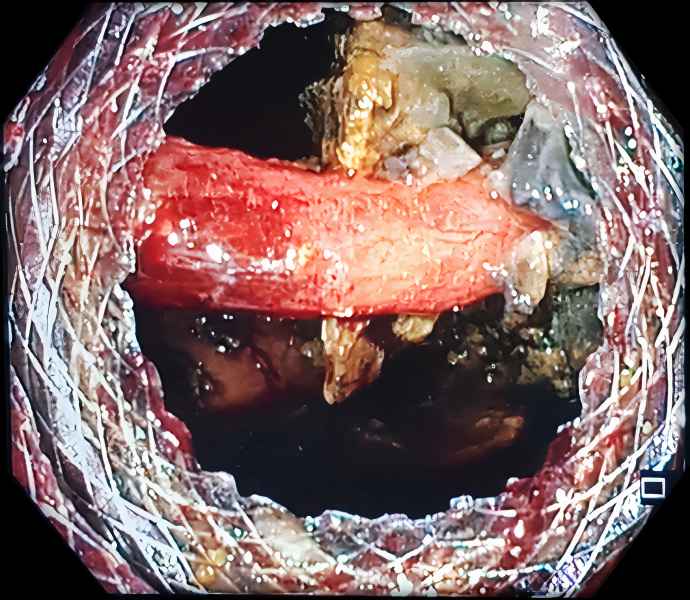

An uninvited guest

Fotografia